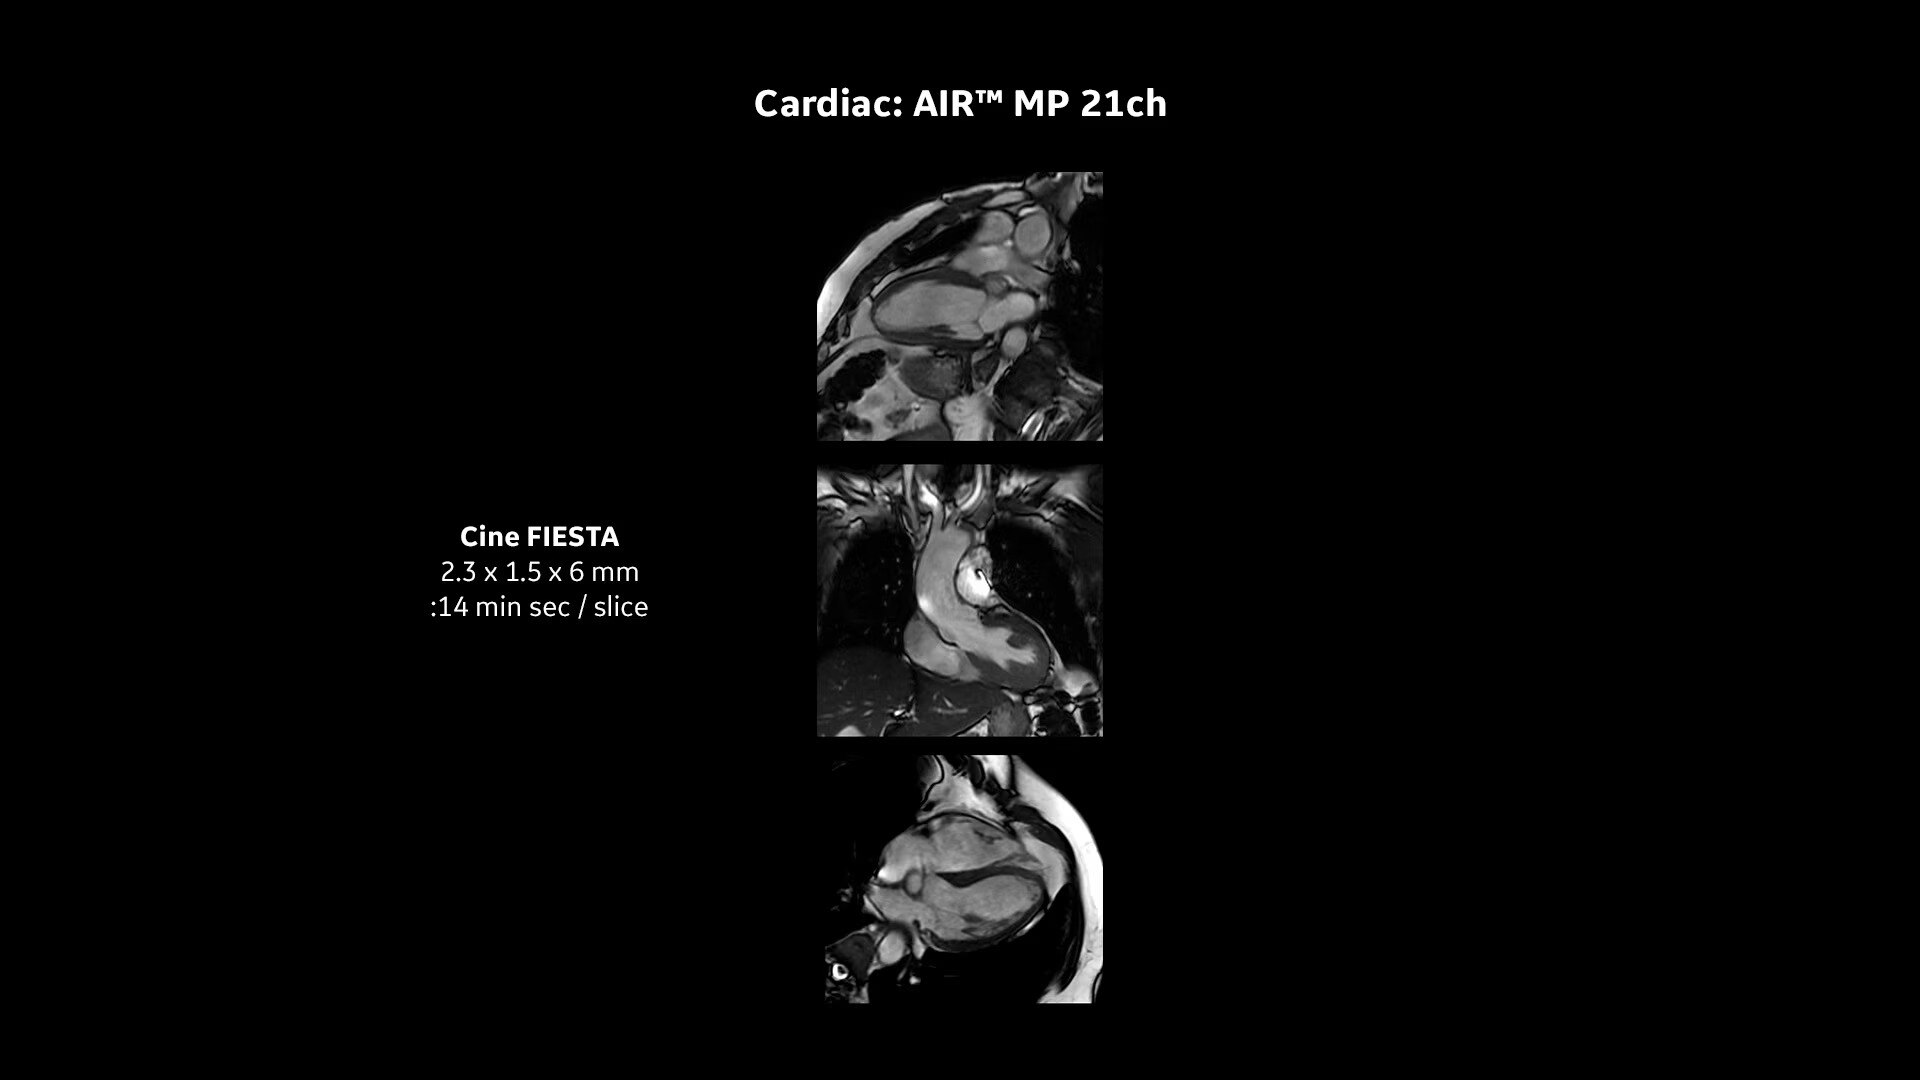

Pioneering innovations: Intelligent coil technology

Transform the patient experience with our industry-leading AIR™ Coils – the closest you can get to total positioning freedom. They are 50% lighter than conventional coil technology and do not need to be strapped around patients, reducing their anxiety and putting them at ease.

Due to their close positioning, AIR™ Coils can also optimize workflow, boost image quality and reduce exam time which is better for technologists too. Combined with AIR Touch™, a smart recognition software which selects the best coil and element configuration for every scan, all users can ensure consistent results every time.